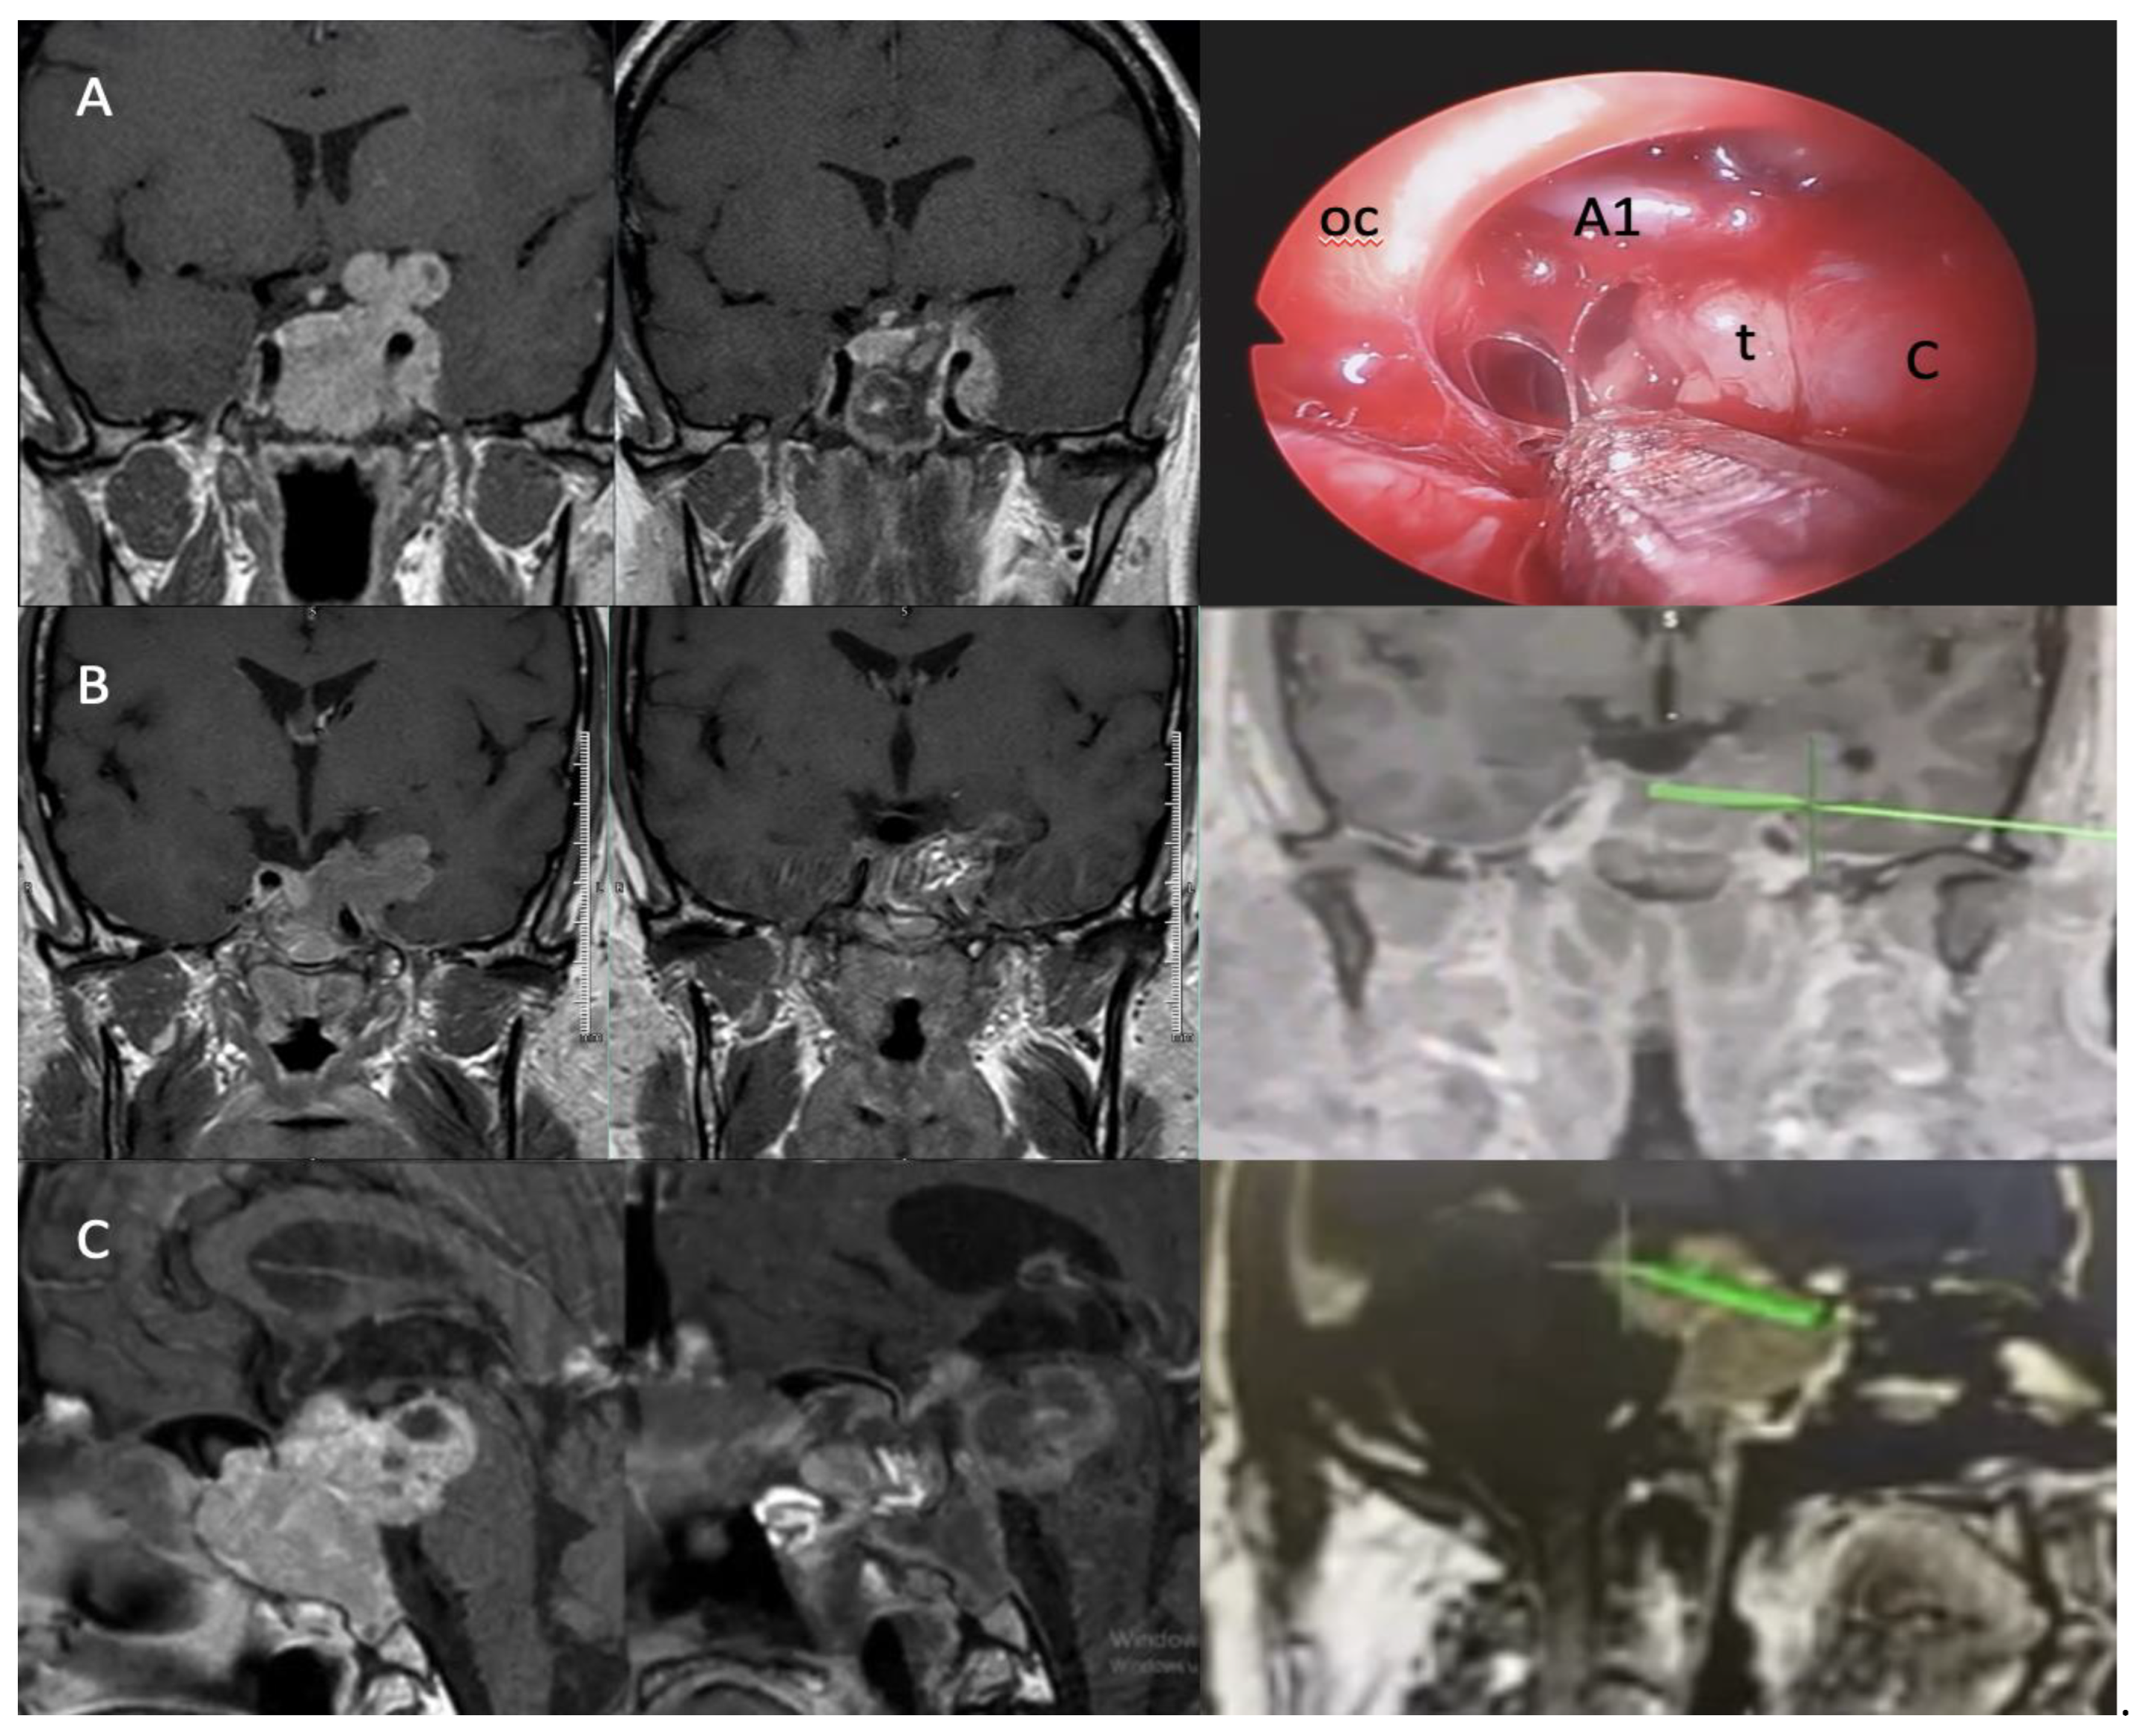

Several studies have highlighted cavernous sinus invasion as a key factor influencing resection outcomes, often necessitating adjuvant radiotherapy or a transcranial approach for optimal management [41,42,43,44]. Tumors invading the lateral compartment of the cavernous sinus or extending superolaterally have lower resection rates, emphasizing the surgical challenges associated with such invasions [45,46]. Cavernous sinus invasion is a key factor influencing surgical outcomes. In our series, 63.3% of the tumors exhibited Knosp grade 3–4 invasion, with higher Knosp grades correlating with lower resection rates. Although previous studies indicate that Knosp grading alone does not preclude GTR, our findings underscore the considerable challenge of achieving complete resection in cases with extensive cavernous sinus involvement. With increasing surgical experience, the resection rates of tumors extending into the temporal lobe or retroclival region via the EEA have improved.(Figure 3) However, for tumors with suprasellar extension into other anatomical regions, additional transcranial surgery may still be required.

Figure 3. A. Intraoperative view of a Zone 3 tumor with NTR and its extension posterior to the carotid artery and into the temporal region. B. Demonstration of the EEA boundary in the temporal region using intraoperative navigation, along with preoperative MRI and postoperative MRI after GTR. C. NTR of a retroclival-extending GA using intraoperative navigation, with preoperative and postoperative MRI images. oc: optic chiasm, t: tumor, C: Carotid artery.